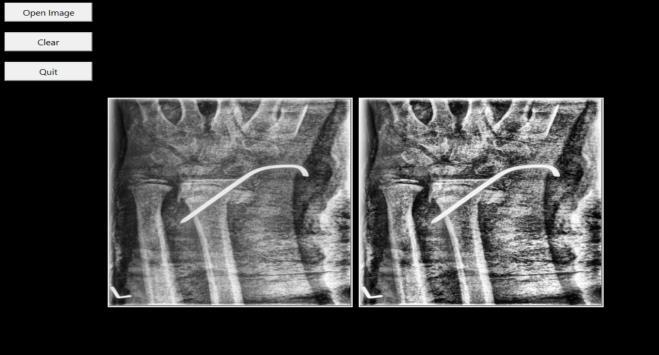

ThefirststageofthesysteminvolvesacquiringtheX-ray imageandpreparingitforfurtheranalysis.Theuseruploads anX-rayimageofthefracturedbonethroughagraphicaluser interface developed using Tkinter. Once the image is uploaded,itisconvertedintoastandardgrayscaleformatto simplifyprocessing.SinceX-rayimagesoftensufferfromlow contrast and noise, a preprocessing step is applied using CLAHE(ContrastLimitedAdaptiveHistogramEqualization). Thistechniqueenhancestheimagecontrastbyredistributing the brightness values, thereby improving the visibility of boneedgesandfracturelines.Theenhancedimageisthen resizedandnormalizedaccordingtotheinputrequirements oftheYOLOv8model.Thispreprocessingstepensuresthat the model receives high-quality and consistent input data, resultinginmoreaccuratefracturedetection.

I. The user provides an X-ray image through the system’sGUI.

II. ThesystempreprocessestheimageusingCLAHEto improvecontrastandclarity.